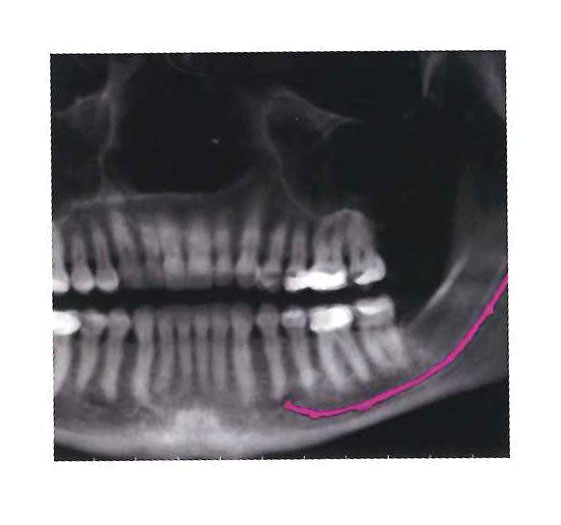

Extraction of Wisdom Teeth

The extraction of wisdom teeth is a procedure to remove one or more wisdom teeth, the four permanent adult teeth in the back corners of the top and bottom of your mouth. Most people have these teeth removed for a number of reasons including pain, discomfort, inflammation, infection or causing damage to neighboring teeth. The surgery is the removal of gum tissue that covers the tooth, detaching the connective tissue that is between the tooth and the bone and finally, removing the tooth and suturing the gum line.